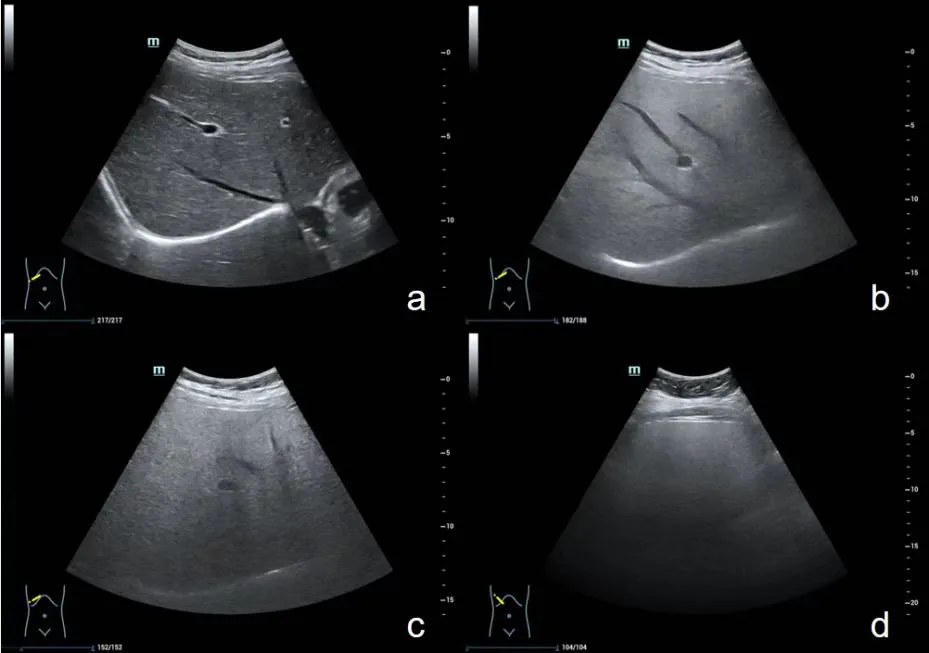

图片2.png

a图正常肝脏   b图轻度脂肪肝   c图中度脂肪肝   d图重度脂肪肝

轻度:肝回声增强,后方回声衰减不明显,肝内管道结构显示正常。

中度:肝回声明显增强,后方回声衰减,肝内管道结构显示欠清晰。

重度: 表现为肝脏普遍性增大,形态饱满,肝缘角显著变钝,肝实质回声呈近场显著增强,远场2/3衰减呈低回声或无回声,后缘轮阔显示不清,整个肝区透声性差,似有一层薄雾,肝内管状结构、膈肌显示很差或不能显示。